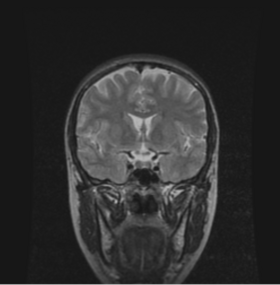

BRAINSMush uses the Maximize Uniformity Summation Heuristic(MUSH) optimizer, as developed at the University of Iowa, to extract the brain and surface CSF from a multi-modal imaging study. It forms a linear combination of multi-modal MR imaging data to make the signal intensity within the brain as uniform as possible. This resulting image is then thresholded to obtain the brain and surface CSF region.

MUSH uses a T1-weighted and T2-weighted image as its inputs, and their mean and variance are calculated. A linear combination is then found that approaches the desired mean and variance( by default 1000.0 and 0.0, respectively) by only varying the coefficients a and b in the following equation: